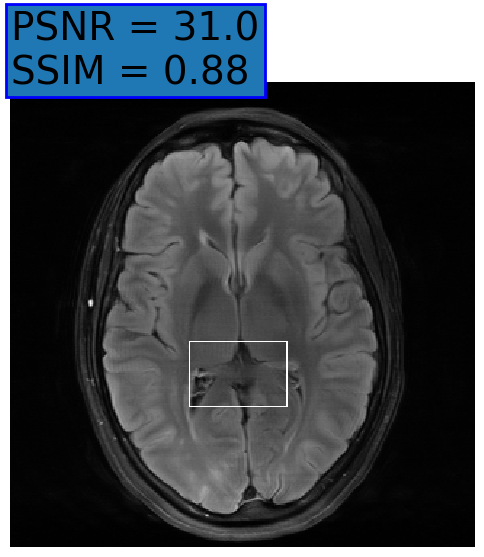

Figure 3: Reconstructions results. Rows 1 and 3: Examples of comparing the ground truth (GT) fully sampled image to the reconstructed images obtained by the three models (1-3), NPB-REC, baseline, E2E-VarNet trained with Dropout, and the NPB-REC std. map at accelerations R=4𝑅4R=4, R=8𝑅8R=8, respectively. Rows 2 and 4: The corresponding annotated ROIS of Nonspecific white matter lesions.

Fig. 3 presents examples of reconstruction results obtained by (1) our NPB-REC approach, (2) the baseline, and (3) Monte Carlo Dropout, for equispaced masks with two different acceleration rates R=4𝑅4R=4 and R=8𝑅8R=8. The reconstructed images predicted by the three models are smoother than the reference image. This is due to the fact that all the models were trained with SSIM loss, which tends to produce overly smooth reconstructions while preserving the diagnostic content and the anatomical features Sriram et al. (2020a). These images can be enhanced by dithering the image by adding a small amount of random Gaussian noise to produce a more textured reconstruction, as proposed in Sriram et al. (2020b).

Table 1 presents the mean PSNR and SSIM metrics, calculated over the whole inference set, for the three models. Our NPB-REC approach achieved significant improvements over the other methods in terms of PSNR and SSIM (Wilcoxon signed-rank test, pmuch-less-than\ll1e-4, except for SSIM values in line W, R=4𝑅4R=4 where they are roughly the same for NPB-REC and Baseline). The improvement in the reconstruction performance can be noted both quantitatively from the metrics, especially for masks with acceleration rate R=8𝑅8R=8, and qualitatively via the images of annotations, where our results show less smoothness than those obtained by Dropout.